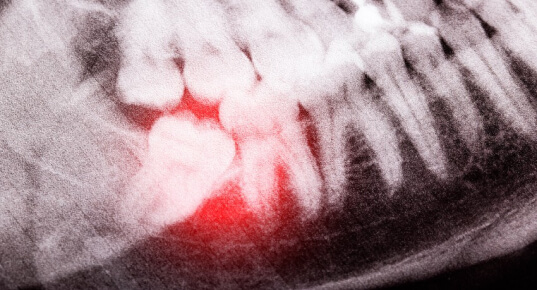

Cirurgia do Siso

A cirurgia de extração de sisos é um procedimento odontológico realizado para remover os terceiros molares. Esses dentes geralmente erupcionam entre os 17 e 25 anos, e sua extração pode ser necessária em vários casos.